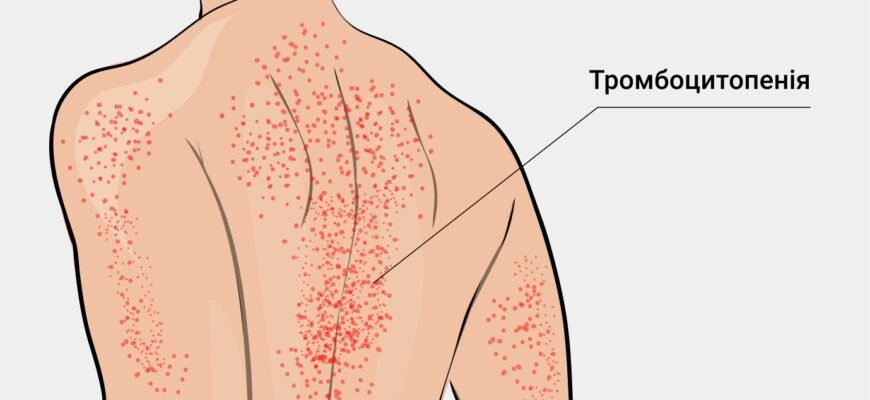

Тромбоцити підвищені у дитини: про що це може свідчити? Почнемо без зайвих прелюдій: якщо ви помітили, що тромбоцити підвищені у дитини, це може бути сигналом

Тромбокрит підвищені у дитини: все, що потрібно знати Тромбокрит підвищені у дитини — звучить страшнувато, чи не так? Або ж не так страшно, як незрозуміло.

Тромбокрит підвищений у дитини: що це значить? Тромбокрит підвищений у дитини – це питання, яке може викликати тривогу у батьків. Чи це серйозно?